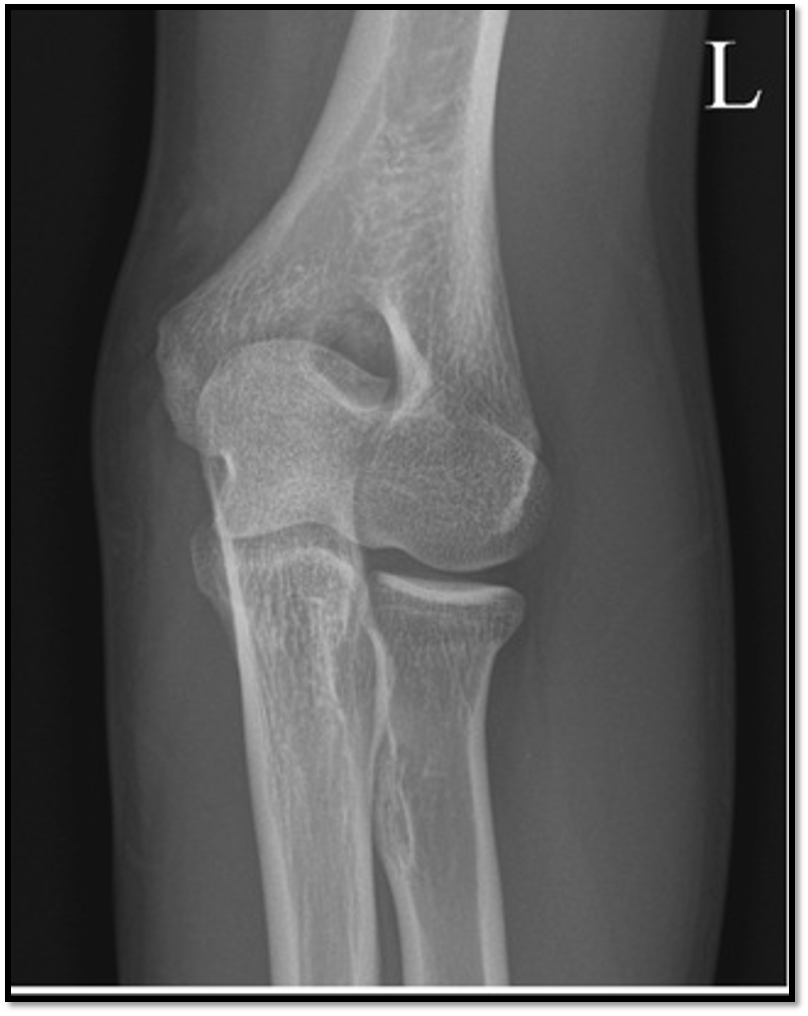

9

AP elbow criteria

A

Medial and lateral humeral epicondyles

are in profile

* 1/4” overlap of radial head on ulna

* 50% of the radius at the radial

tuberosity is superimposed by the ulna

* Capitulum-radial joint space is open

↳have all 3 jointson same plane

* Radius and ulna are parallel